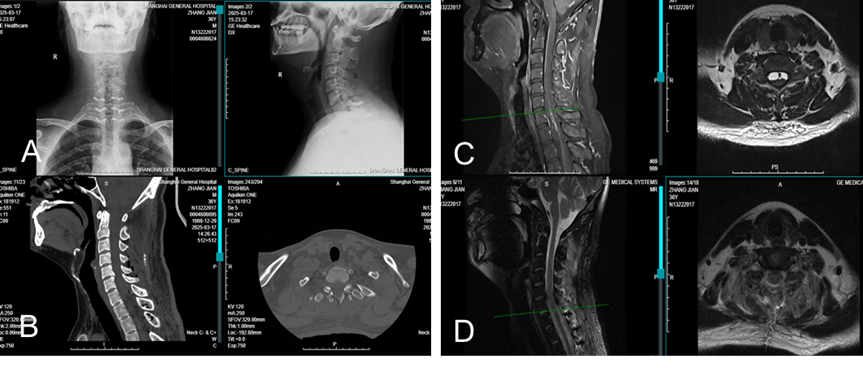

术后3天引流50ml以下拔除引流管,术后复查X线、CT及核磁共振并与术前比较

图示:A.术后X线正侧位片;B:术后CT矢状位及横断面;C:术前颈椎核磁示椎管内肿瘤占位;D.术后复查核磁提示肿瘤彻底清除。

术后病理:神经鞘瘤